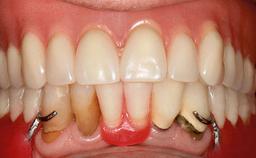

Surgical treatment of a 67-year-old male patient exhibiting an extended edentulous space in the anterior maxilla after the removal of three hopeless incisor teeth.

The video demonstrates implant placement using a surgical stent according to the principle of prosthodontically driven implant placement. The deficient ridge is augmented with locally harvested autologous bone chips, a superficial layer of xenogenic DBBM particles and a resorbable collagen membrane. The surgery is completed with a precise, tension-free primary wound closure.

The case concludes with the presentation of the final prosthesis and the esthetic outcome, demonstrating stable soft tissue conditions and stable bone crest levels at the 3-year follow-up.